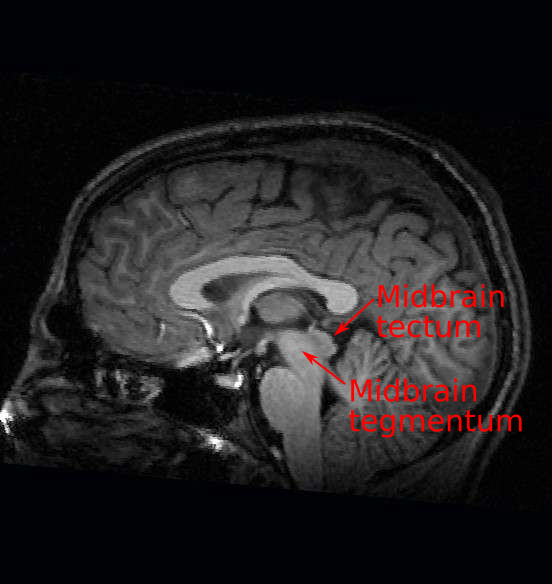

Midbrain

The tectum of the midbrain, which is latin for ‘roof’ contains the superior and inferior colliculi and is important for processing visual and auditory information as well as shaping motor commands for orienting the head and body.

Ventral to the cerebral aqueduct through which cerebral spinal fluid circulates, you will find the tegmentum of the midbrain which contains the —>